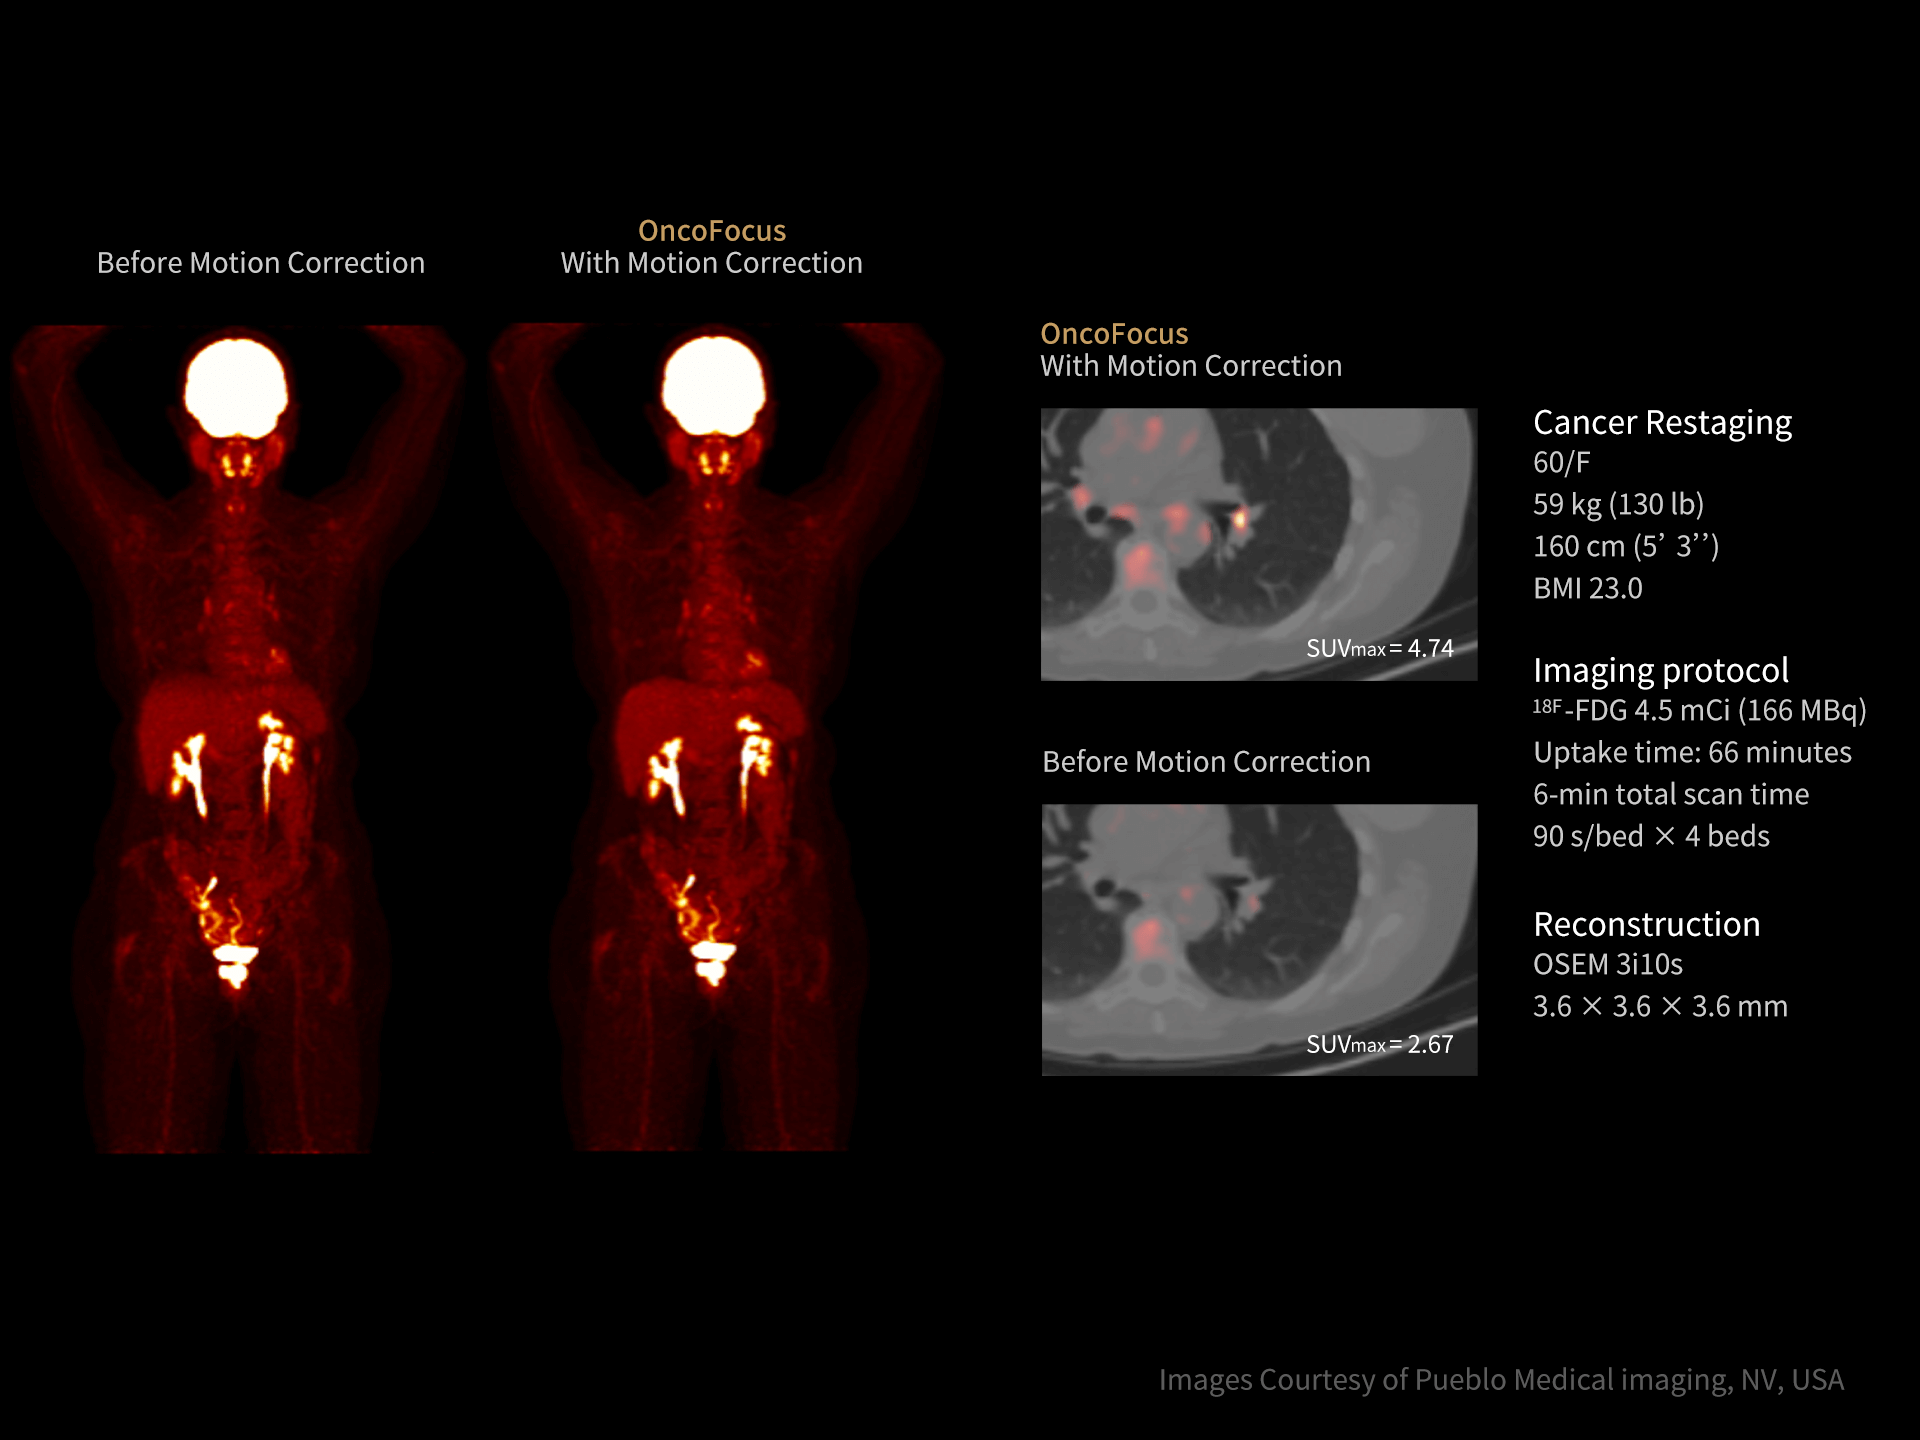

Rezoluția TOF de 219 ps crește claritatea imaginilor și detectabilitatea leziunilor mici, oferind un avantaj clinic major în diagnosticul PET/CT.

Rezoluție TOF de 219 ps pentru detecție precisă

Rezoluția TOF avansată de 219 ps îmbunătățește vizibilitatea leziunilor mici și acuratețea cantitativă.